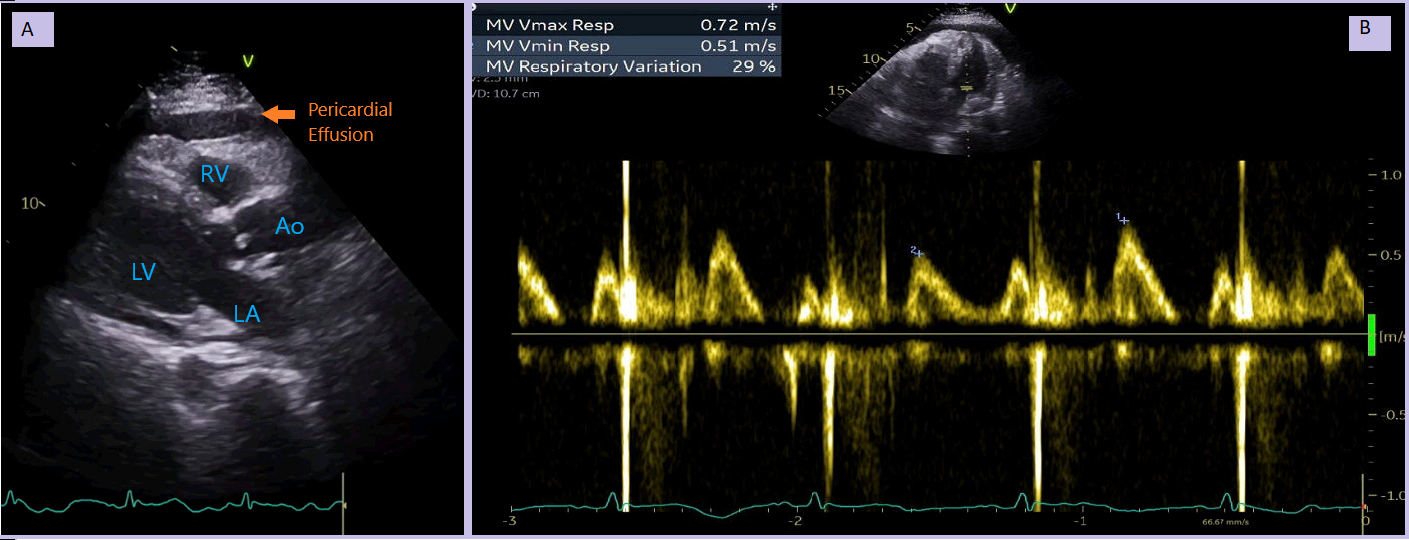

Repeat TTE showed a moderate pericardial effusion (2 cm) near the RV free wall. There was no RV diastolic collapse, but >25% MV E-wave respiratory variation was seen.